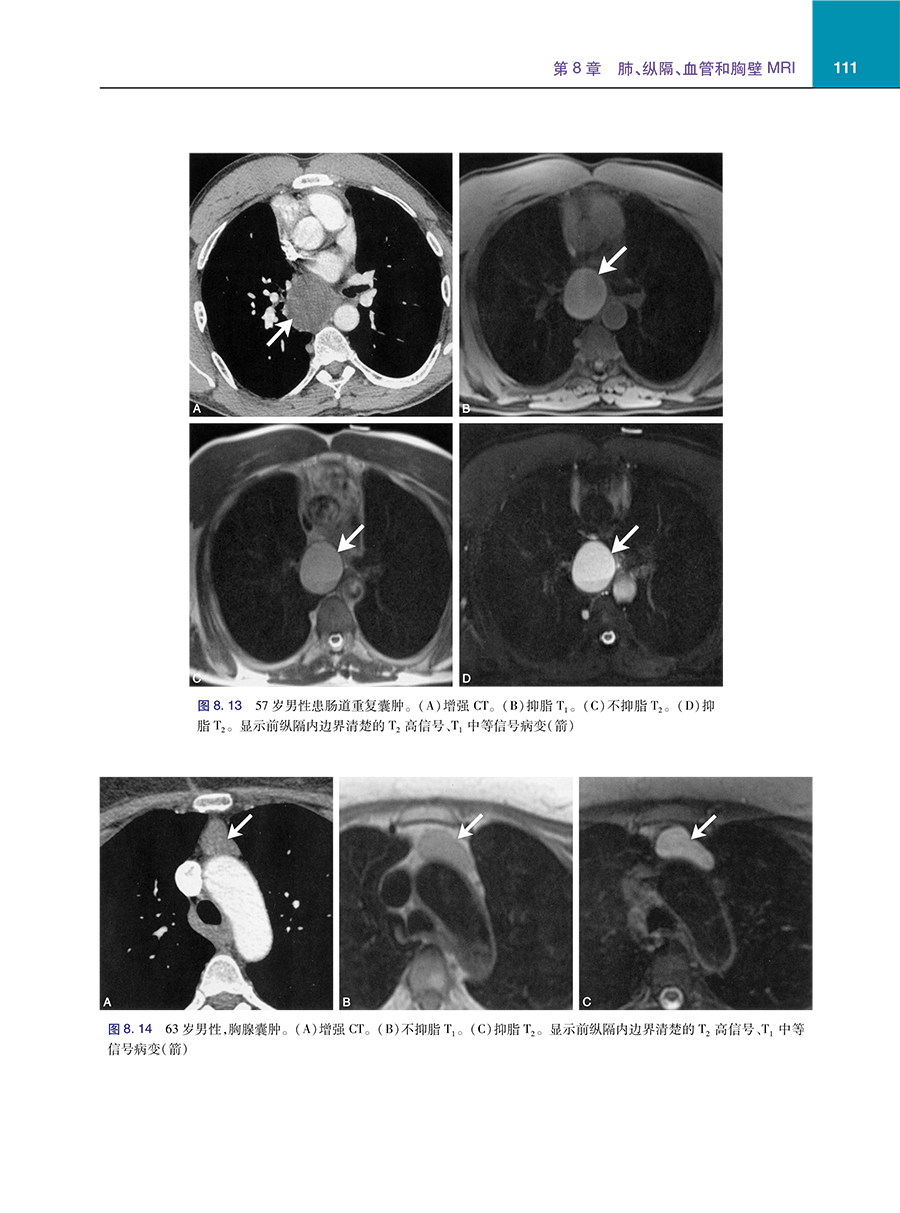

4 呈现1,500多张高质量图像,可清晰地阐释问题解析的内容。

5 专注于胸部影像问题解析所需的核心知识,包括解剖学、成像技术、成像方法、按病理和解剖区域以及特殊情况划分的病种。

主要主题包括弥漫性肺病、肺和气道肿瘤、间质性肺病、吸烟相关肺部疾病和心血管疾病。